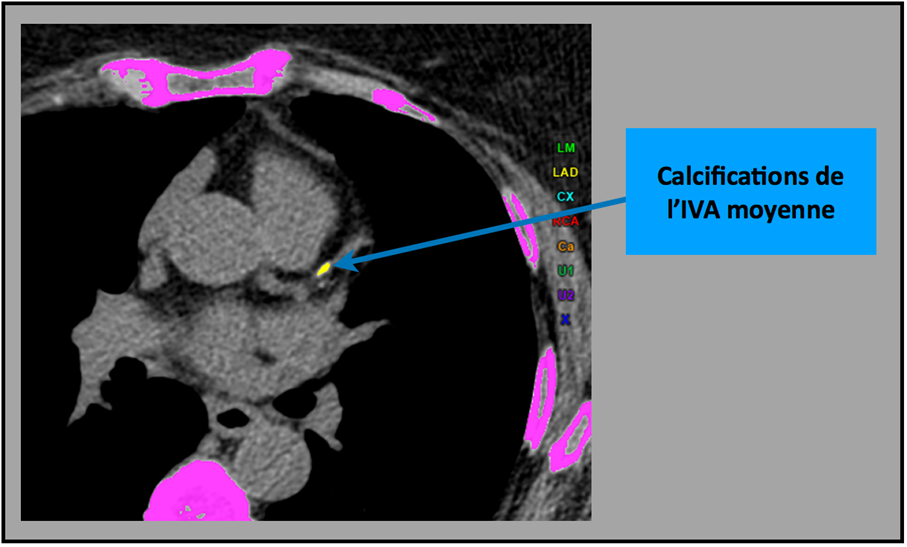

Cet examen consiste en une acquisition unique centrée sur le massif cardiaque avec une apnée courte < 5 secondes ; il peut être réalisé en moins de 10 minutes. L’irradiation est très limitée (< 1 mSv) et ne nécessite pas d’injection de produit de contraste. Il est calculé en sélectionnant toutes les calcifications d’une surface > 1 mm2 ayant une densité > 130 UH (fig. 1). La somme des surfaces de chaque calcification multipliées par leur densité permet d’obtenir le score calcique ou score d’Agaston.

Figure 1. Sélection des calcifications coronaires pour la mesure du score. L’opérateur a sélectionné une calcification de l’artère interventriculaire antérieure et l’ordinateur calcule un score en fonction de la surface et de la densité de cette calcification.